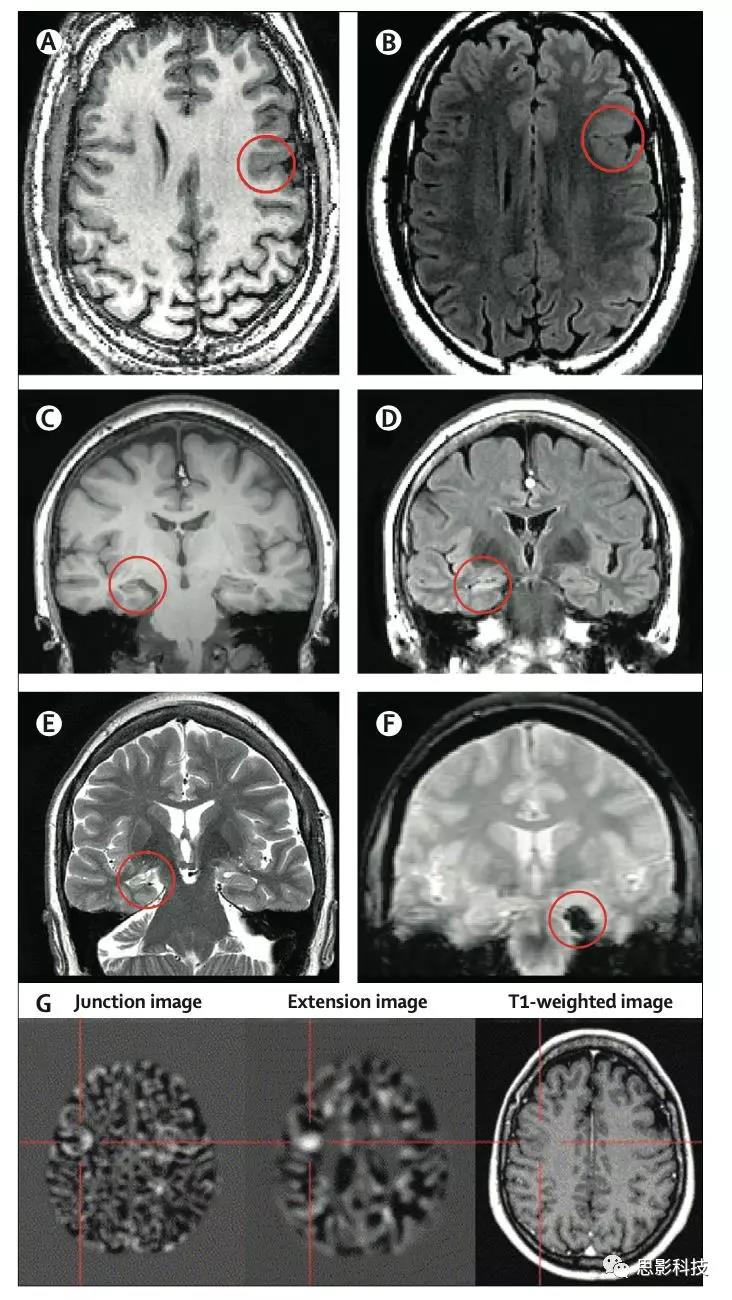

局灶性皮質(zhì)發(fā)育不良伴皮質(zhì)增厚和模糊的灰質(zhì)-白質(zhì)交界, T1加權(quán)成像(A)上(圓圈),在T2FLAIR(B)上呈高信號(hào)。右海馬硬化伴體積損失在T1加權(quán)成像(C)(圓圈),在T2加權(quán)(D)上高信號(hào)強(qiáng)度,和T2加權(quán)成像(E)上內(nèi)部結(jié)構(gòu)的損失。T2*加權(quán)圖像(F)上,左側(cè)顳下回海綿狀瘤(圓圈狀)可以被視為信號(hào)丟失區(qū)。(G)將基于體素的圖像后處理方法應(yīng)用于一名38歲婦女的T1等體素序列MRI數(shù)據(jù),能清楚顯示交界圖像(模糊的灰質(zhì)-白質(zhì)交界)和延伸圖像(灰質(zhì)異常延伸至白質(zhì))上的局灶性皮質(zhì)發(fā)育不良。相應(yīng)的切片顯示在原始T1加權(quán)圖像上。(A—F)在3T掃描儀上獲得(A,C)三維快速損毀梯度回波T1加權(quán)序列(體素0.9375×0.9375×1.1mm),(B)軸向和(D)斜冠狀T2FLAIR序列(體素:0.9375×0.9375×5mm),(E)使用螺旋槳技術(shù)的斜冠狀位T2加權(quán)序列(層面分辨率為0.43×0.43mm,層厚為2mm)和(F)冠狀快速梯度回波T2加權(quán)序列(層面分辨率為0.9375×0.9375mm,層厚為5mm)。對(duì)于所有圖像,圖像的左側(cè)=大腦的右側(cè)。

基于體素的形態(tài)學(xué)分析(VBM)最初應(yīng)用于T1加權(quán)圖像,用于組間灰白質(zhì)的定量分析,隨后用于個(gè)體與對(duì)照組的比較。初步研究結(jié)果表明,27例局灶性皮質(zhì)發(fā)育不良患者中有21例被正確識(shí)別?;隗w素的分析已經(jīng)被應(yīng)用于T2弛豫圖和FLAIR圖像,以提高對(duì)局灶性皮質(zhì)發(fā)育不良和MRI陰性者異常的檢測(cè)靈敏度。通過(guò)基于VBM的形態(tài)測(cè)量分析程序產(chǎn)生一個(gè)交界圖以突出灰白色物質(zhì)邊界的模糊和一個(gè)延伸圖以描繪異常深的腦溝(圖2G),提高了對(duì)局灶性皮質(zhì)發(fā)育不良的檢測(cè)率。在一項(xiàng)研究中,形態(tài)計(jì)量學(xué)分析MRI掃描結(jié)果進(jìn)行了補(bǔ)充,與許多其他圖像分析儀器一樣,這些方法還沒(méi)有被廣泛采用,專家單位以外的臨床醫(yī)生通常認(rèn)為這些方法復(fù)雜且不直觀。

7:在癲癇手術(shù)路徑中整合多模式三維成像立體腦電圖植入計(jì)劃。每個(gè)電極以單獨(dú)的顏色表示。所有圖像均從左后外側(cè)方向拍攝。

(A)從釓增強(qiáng)T1加權(quán)MRI提取靜脈(藍(lán)色)和從CT血管造影提取的動(dòng)脈(紅色)。

(B)T2加權(quán)FLAIR MRI(紫色)和運(yùn)動(dòng)(綠色)和語(yǔ)言(橙色)區(qū)域(從功能MRI鑒定)識(shí)別出的病變。

(C)中的病變,運(yùn)動(dòng)和語(yǔ)言區(qū)域顯示在T1加權(quán)MRI上。